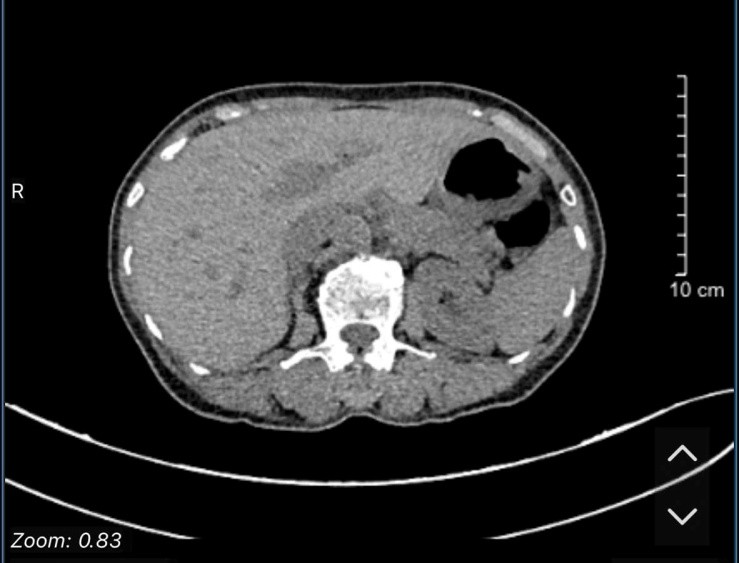

Case lâm sàng: Ứng dụng trí tuệ nhân tạo (Artificial intelligence – AI) trong chẩn đoán và điều trị sớm Ung thư phổi tại Trung tâm Y học hạt nhân và Ung bướu, Bệnh viện Bạch Mai

Theo GLOBOCAN 2022, ung thư phổi đứng đầu về số ca mới mắc (2.480.301 ca mới mắc chiểm 12.4%) và dẫn đầu số ca tử vong (1.817.172 ca tử vong chiếm 18.7%) trên toàn thế giới.  Tại Việt Nam tỷ lệ mắc ung thư phổi xếp thứ ba 13,5% lệ tử vong...